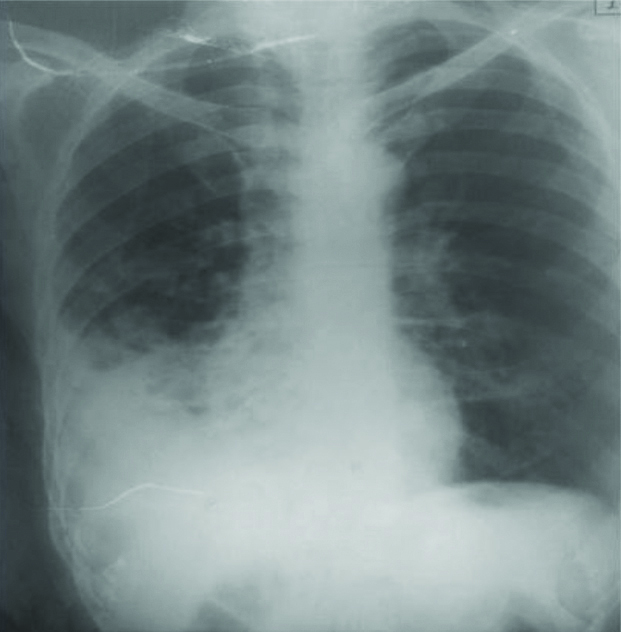

Laboratory investigations revealed Haemoglobin (Hb or Hgb) was 8.7 g/dL, Total Count (TC) was 10,700, Differential Leucocyte Count (DLC)-Neutrophils/Lymphocytes/Eosinophils/Monocyte (N/L/E/M) was 75/16/04/05, Erythrocyte Sedimentation Rate (ESR) was 76 mm/hr. Current X-ray chest was suggestive of right lower zone homogenous opacity [Table/Fig-1]. Computed Tomography (CT) thorax suspected of multiple nodular opacities in both lung fields predominantly posterior segment of right upper lobe, bronchiectactic changes in bilateral upper lobes and superior segment of bilateral lower lobes. Tracheal diameter measures approx. 22 mm Anteroposterior (AP) and 34 mm transverse (Max. luminal- ML) just above the carina and right main bronchus measures 28 mm suggestive of mildly dilated trachea and right main bronchi [Table/Fig-2a,b,3 and 4].

Chest X-ray-PA showing non homogenous opacity in right lower zone with reticular opacities in bilateral lung fields.